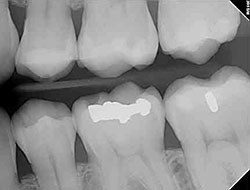

Digital X-Rays

Using the most advanced dental technology possible is just as important as staying up-to-date on the latest treatment techniques. Because our dental practice is dedicated to providing you with the safest and most convenient treatment options available, we utilize advanced digital X-ray technology in our office.

Digital X-rays provide several advanced imaging options that are designed to save time, provide clearer dental photos, and expose patients to less radiation than with traditional X-ray technology.